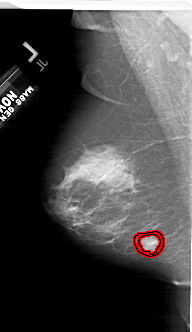

A_1622_1.LEFT_CC

LEFT_CC LINES 6841 PIXELS_PER_LINE 3301 BITS_PER_PIXEL 12 RESOLUTION 43.5 OVERLAY

FILE: A_1622_1.LEFT_CC.OVERLAY

TOTAL_ABNORMALITIES 1

ABNORMALITY 1

LESION_TYPE MASS SHAPE IRREGULAR MARGINS SPICULATED

ASSESSMENT 5

SUBTLETY 5

PATHOLOGY MALIGNANT

TOTAL_OUTLINES 2

BOUNDARY

CORE